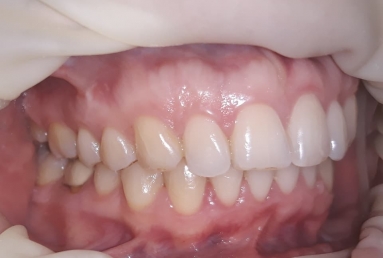

SAPPHIRE ORTHODONTIC DEVICE

Orthodontic treatment, external sinus lifting, dental implant and zirconium crown.